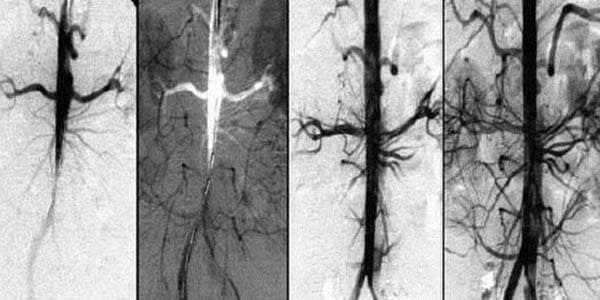

Il trattamento dei disturbi circolatori consiste nel liberare i vasi e le arterie dalle impurità accumulate e nel ripristinare il normale flusso sanguigno.

Il ripristino di una normale circolazione sanguigna è un processo complesso che dipende dalle condizioni di tutti i vasi sanguigni del corpo. Il risanamento di questi ultimi consente di migliorare significativamente sia lo stato di salute generale che la qualità della vita.

2. Migliora la circolazione sanguigna

Riduce il rischio di coagulazione del sangue e ha un effetto antiossidante.

3. Aumenta la forza e ripristina l'elasticità delle pareti vascolari

Previene la formazione di placche e riduce significativamente il rischio di ictus.